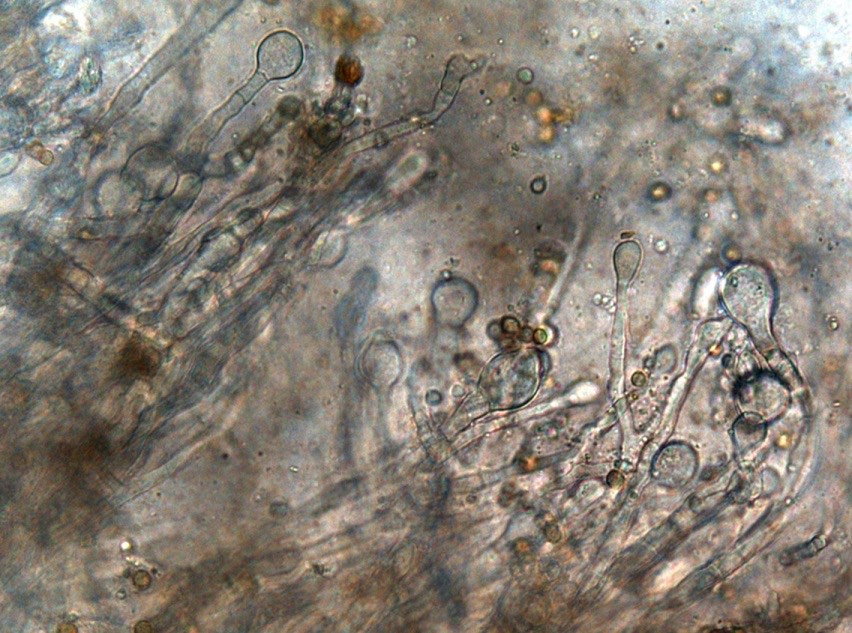

2035. В микропрепарате из пораженных тканей верхнечелюстной пазухи обнаружена конидиальная головка aspergillus spp., представленная